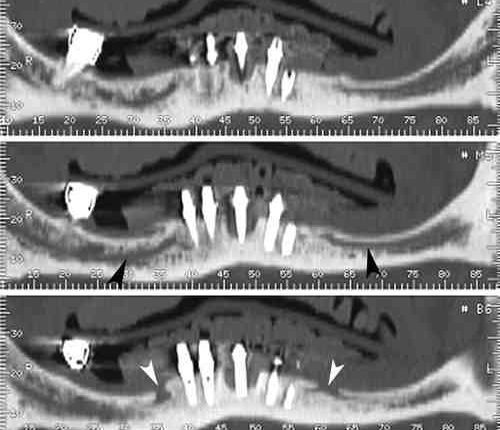

What type of radiographs are taken before implant surgery?

Periapical and panoramic radiographs are commonly used in implant dentistry and are two-dimensional (2D) representations of three-dimensional (3D) objects. Periapical radiographs are intended to give an impression of the whole tooth or implant, including the apex and surrounding bone.

Prior to the advent of digital diagnostic imaging, much speculation was concerned with implant dentistry. CT scans eliminate all of that. Implants placed in the lower jaw must not interfere with the mandibular nerves. Alternatively, permanent paresthesia may occur.